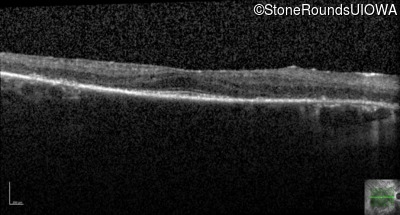

Optical Coherence Tomography - Left - 20/20 -2

Exemplar / OCT Stack

OCT Stack